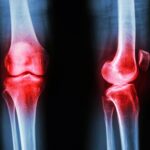

Additionally, there is a significant relationship between insulin sensitivity and a child’s overall health. Insulin sensitivity refers to how effectively the body responds to insulin, and it has substantial implications for metabolic health. Poor dietary choices can lead to decreased insulin sensitivity, increasing the risk of metabolic disorders such as obesity and type 2 diabetes. Teaching children about the impact of sugar-laden snacks and highly processed foods fosters an understanding of how nutrition affects their body. By making informed dietary choices, children gain insight into managing their health proactively, which is a vital skill as they grow.